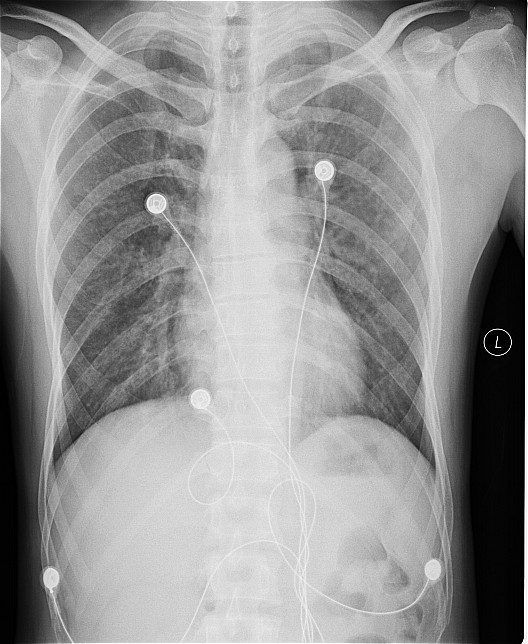

一钨矿工厂因有毒气体泄漏(据说是硝酸)造成十多名工人中毒,均出现不同程度的咳嗽,气逼,心跳加快等中毒症状.其中有几例患者胸片出现小点片状,结节状阴影.是此次中毒引起的肺部改变还是原来就患有矽肺病或其它病变.

肺水肿,及原来就患有矽肺病

原就有的矽肺,未见中毒性肺水肿

支持矽肺,未见肺水肿.建议治疗后复查

矽肺,部分胸片可见肺水肿。治疗复查